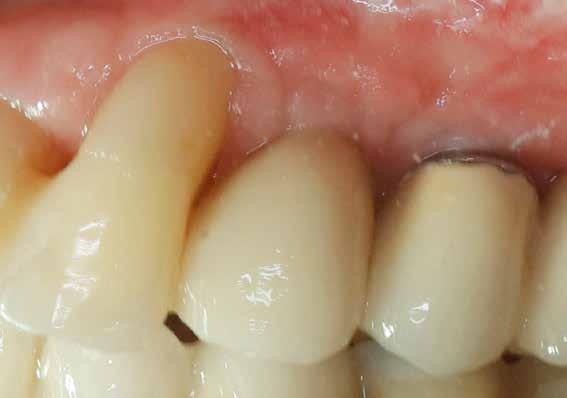

A 2020 januárjában elkezdett kezeléssorozat befejezését az év márciusában, hazánkba is begyűrűző Covid-19 pandémia késleltette, így kb. 6 hónap gyógyulás után láttunk hozzá az emergencia profil és a gingivális zenit ideiglenes koronával történő formázásához (11. és 12. kép). A 3 hetente végzett apró alakításokkal sikerült megfelelő ínyprofilt kialakítani, a „rózsaszín esztétika” a páciens számára is megfelelő volt. A bal felső nagymetsző fog meziális kompozit tömés cseréjét követően, individualizált nyitott kanalas lenyomati fejet készítettünk: az akrilát ideiglenes korona profilját átlátszó szilikonnal lemásoltuk, majd a körszimmetrikus gyári lenyomati fej és az ideiglenes korona kontúrja közötti hézagot folyékony kompozittal töltöttük ki (13. kép). Az így készített egyéni lenyomati fejjel vettünk lenyomatot a végleges, kerámialeplezésű cirkónium-dioxid vázas, átmenő csavaros rögzítésű koronához. (A fogtechnikai munkát Nébl Péter fogtechnikusmester készítette.), (14., 15., 16 és 17. képek).

A kész korona átadásakor a páciens elégedett volt az esztétikával, az azóta eltelt évben rendszeres kontrollokon jelent meg, melyek során meggyőződtünk a kemény- és lágyszövetek stabilitásáról (18. és 19. képek).

A fent bemutatott, „socket-shield” technikával végzett esethez hasonló, speciális esetek ellátása jelenleg is zajlik a rendelőnkben. Tény, hogy az indikációs kör szűk mivolta miatt ritkán alkalmazható, azonban egyre gyarapodó tapasztalataink szerint ezekben a különleges helyzetekben biztonságos, kiszámítható módszer a frontrégió implantátummal történő pótlására.